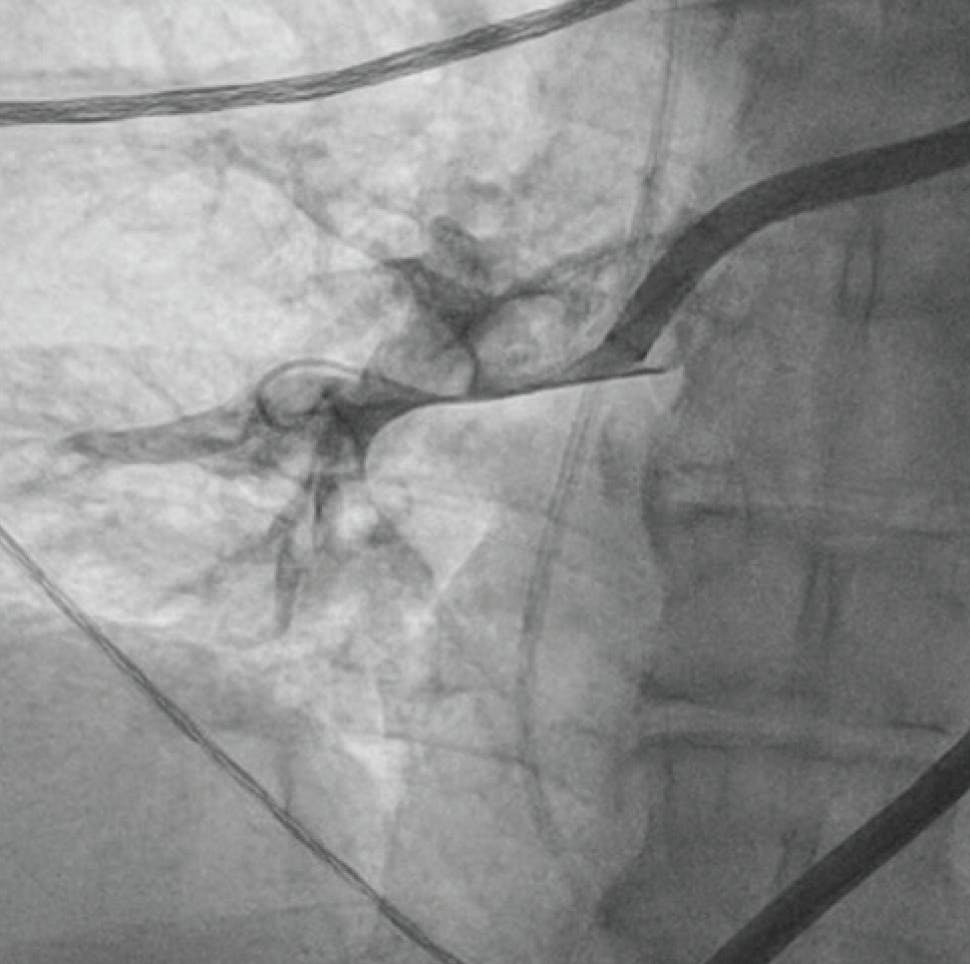

A man in his late 50s with no cardiac history and who was a former smoker presented to our department for acute chest pain, with symptom onset 2 hours prior. The pain was typical and an electrocardiogram showed an anterior ST-segment elevation myocardial infarction (STEMI), so he was immediately taken to the cath lab. A coronary angiogram showed complete left anteriror descendant (LAD) coronary occlusion in the medial part (Figure 1) with TIMI flow 0. After coronary wiring and a soft predilation, we appreciated a great thrombotic burden occupying almost one-third of the vessel (Figure 2).

Figure 1. Angiographic view (caudal 35°) showing complete LAD occlusion in the medial part.

Figure 2. Angiographic view (cranial 40°) showing incomplete flow restoration with high thrombus burden in the LAD after wiring passage and soft predilation.